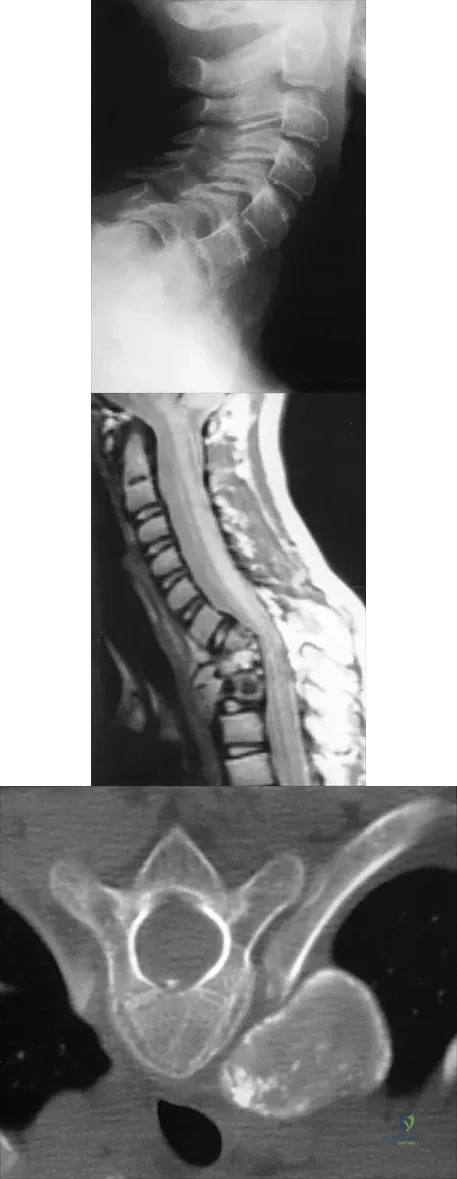

Question 68

A 10-year-old girl has been referred for evaluation of a prominence at the lower cervical spine. The patient is asymptomatic, and the examination reveals no evidence of neurologic abnormality. A radiograph and CT scans are shown in Figures 12a through 12c. What is the most likely diagnosis?

Explanation